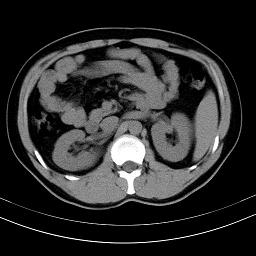

标题: CT18388:肝脏膈肌间隙内大量脂肪密度影 [打印本页]

标题: CT18388:肝脏膈肌间隙内大量脂肪密度影

是脂肪不是气体,有时候会碰到这样的病人,脂肪过多吧。

腹腔脂肪沉积过多

膈下脂肪沉积。

考虑膈下脂肪沉积。

激素治疗的病人容易脂肪沉积